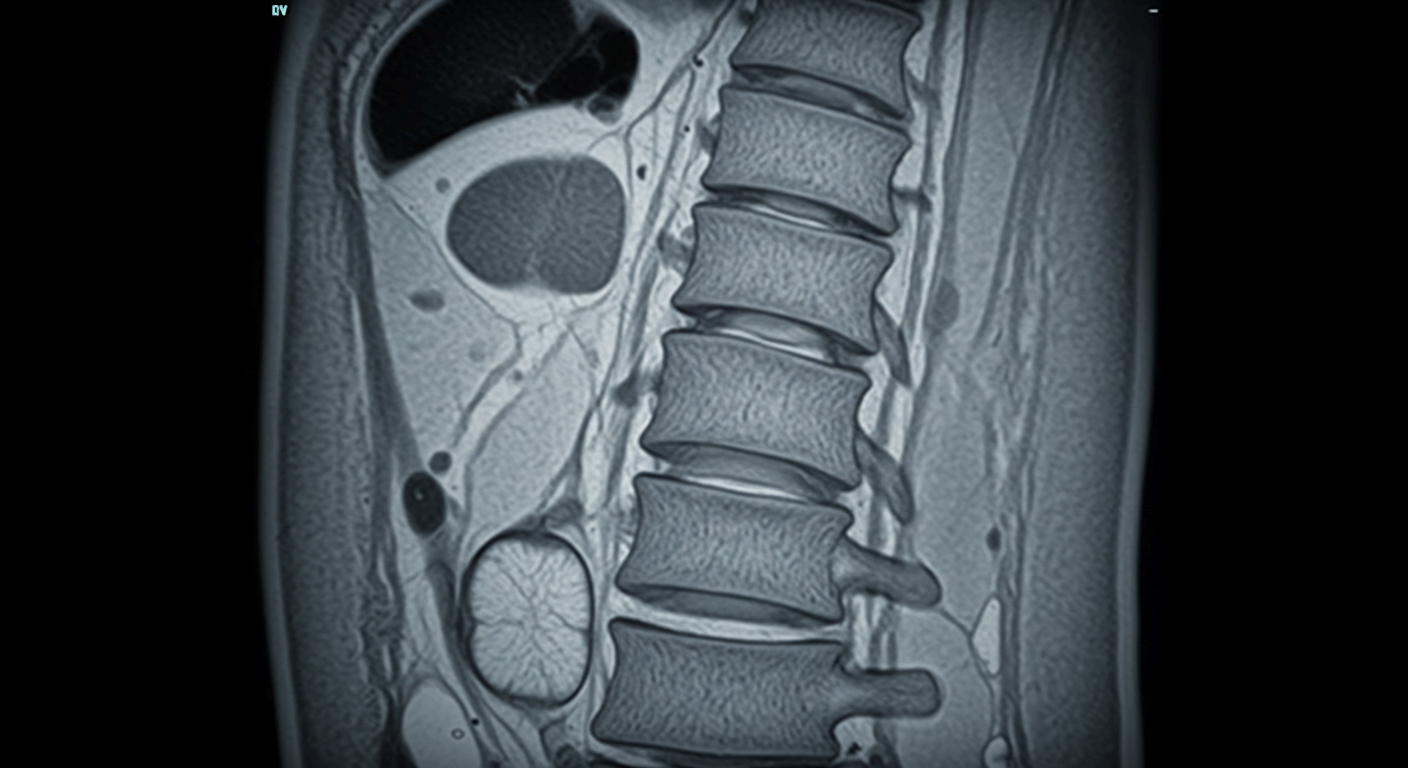

- 허리디스크(추간판 탈출증): 디스크가 신경을 압박해 허리와 다리에 저림·통증 유발

- 척추관 협착증: 신경 통로가 좁아져 다리 마비·통증 발생

| 디스크 | 허리 통증 + 다리 방사통 |

| 협착증 | 오래 걷기 힘들고 앉으면 완화 |